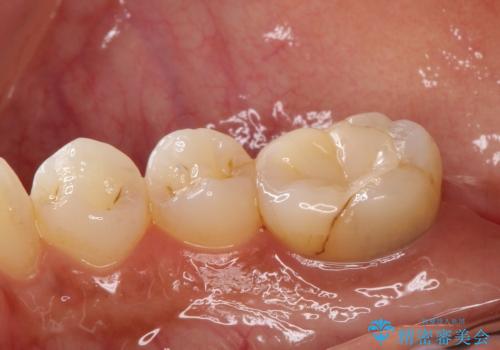

【オールセラミック】奥歯が痛い。根管治療〜被せ物治療

- 奥歯が痛いことを主訴に来院されました。

根管治療を行なったのちオールセラミッククラウンにて修復補綴を行いました。